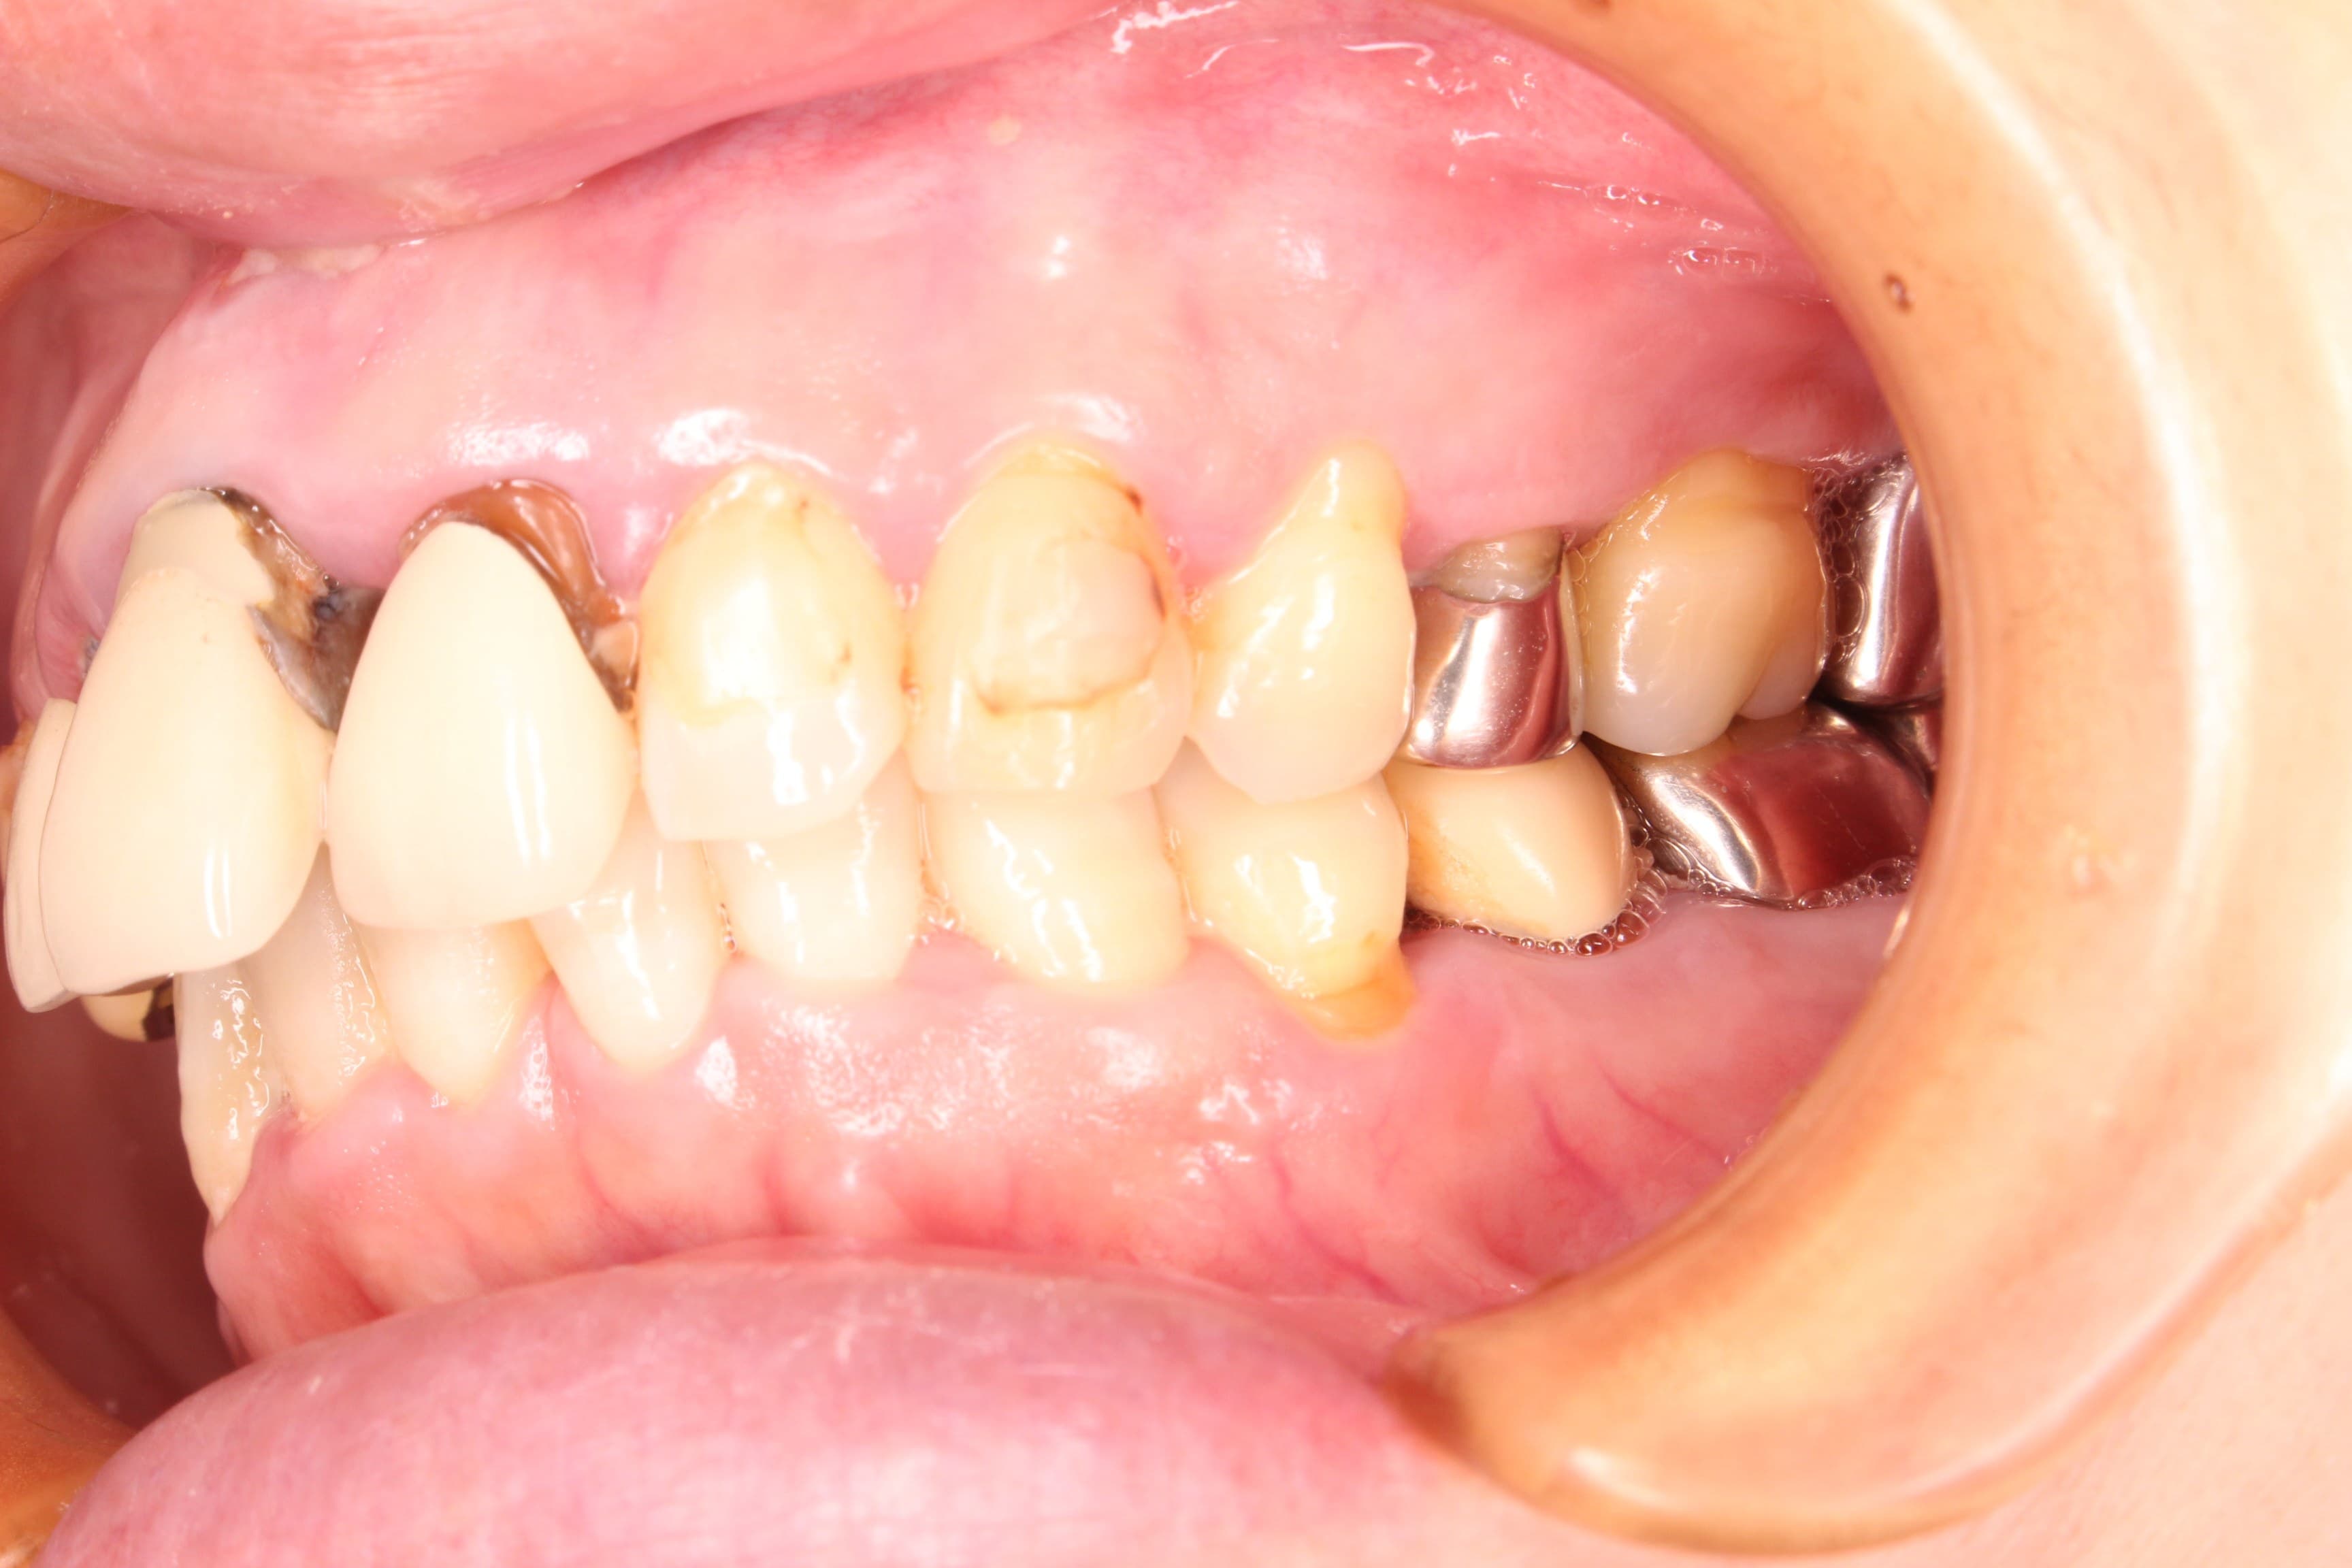

今回ご紹介する歯周専門治療のケースは、50代女性の方です。

虫歯の治療を希望されて来院されました。

口腔内の状態は、虫歯も大きく進行し、歯周病のコントロールもされておらず、出血やプラーク、歯石等の感染物質も大量に付着していた為、虫歯の治療ができる状態ではありませんでした。

虫歯の治療はこれからですが、ブラッシングの精度もかなり高くなり、虫歯や歯周病に対する予防の知識もしっかりと習得して頂く事ができました。